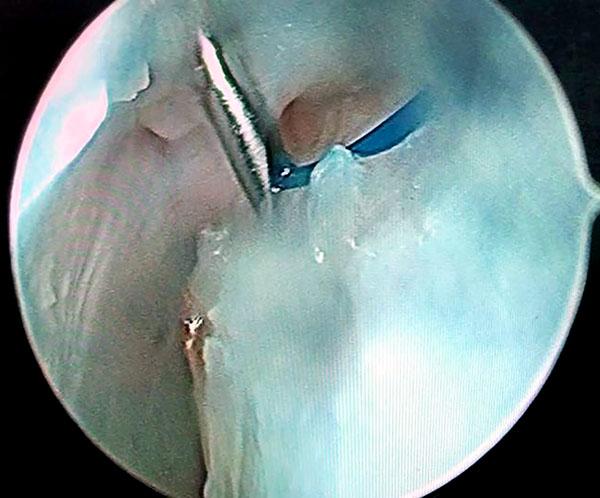

Luego por articulación radiocarpiana, se debrida y estimula el ligamento escafolunar; y si lo amerita realizamos radiofrecuencia del mismo previo a Capsulodesis. Terminado este paso, realizamos la técnica modificada de Mathoulin. Se realiza el pasaje de una sutura prolene 2.0 por medio de una aguja intramuscular desde la cápsula dorsal 1 cm proximal al portal 3/4 y 1 cm cubital (figs. 1 a 4).

Figuras 1 a 4: Muestran visión por portales 6R con ingreso de agujas con hilos desde capsulo hacia el ligamento escafolunar.

Se realiza visión por portal 6r y se pasa la aguja por la cápsula y uno de los sectores dañados del ligamento escafolunar hacia la articulación mediocarpiana donde se rescata la sutura y se retira por el portal MCR con visión MCU. Se repite este paso con otra aguja paralela a la primera que atraviese la cápsula y la otra parte del ligamento escafolunar dañada, y se rescata la sutura por articulación medio carpiana. Las 2 suturas rescatadas por mediocarpiano se anudan de forma simple, y se realiza el deslizamiento de los extremos de las suturas proximales con visión MCU, consiguiendo que el nudo quede anclado por mediocarpiano en el lig. Escafolunar (figs. 5 a 10).

Figuras 1 a 10: Muestran el ingreso de las agujas desde el portal radiocarpiano al mediocarpiano y el retiro de los hilos por el portal MCR con el nudo anclado en espacio mediocarpiano.